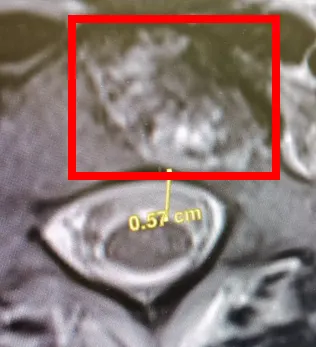

當然除了好消息,肯定也有壞消息。當時除了胸部也同時掃描頸部,發現脊椎也有癌細胞的侵蝕,因此又安排做了整條脊椎的磁共振成像(Magnetic Resonance Imaging),發現一共有三處地方比較危險,其中一處距離脊椎核心只差0.57公分,主治醫師除了安排我去見負責放射治療的醫生,也推薦打補骨針。和放射科醫生討論的結果,決定繼續觀察,雖然已經很接近脊椎核心,但是沒人知道癌細胞是會繼續往核心移動還是換地方,甚至不擴散。主要是因爲之前沒有拍脊椎MRI,所以不知道現在這個情況是去年九月就這樣,還是持續擴散的結果。也因爲這個理由,我拒絕了醫生的推薦,決定暫時不打補骨針。

脊椎切面圖,紅框内為癌細胞侵蝕部分